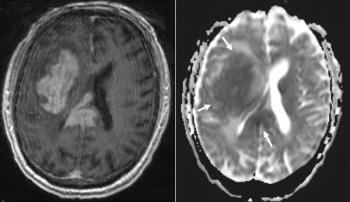

A 35-year-old man presents with severe headaches, and a biopsy is obtained. What is your diagnosis?

A 74-year-old man with a medical history of hypertension, hyperlipidemia, and type 2 diabetes mellitus was found lying on the ground by his family and was brought to the emergency department, where he was found to have left facial drooping and weakness. What is the most likely diagnosis?